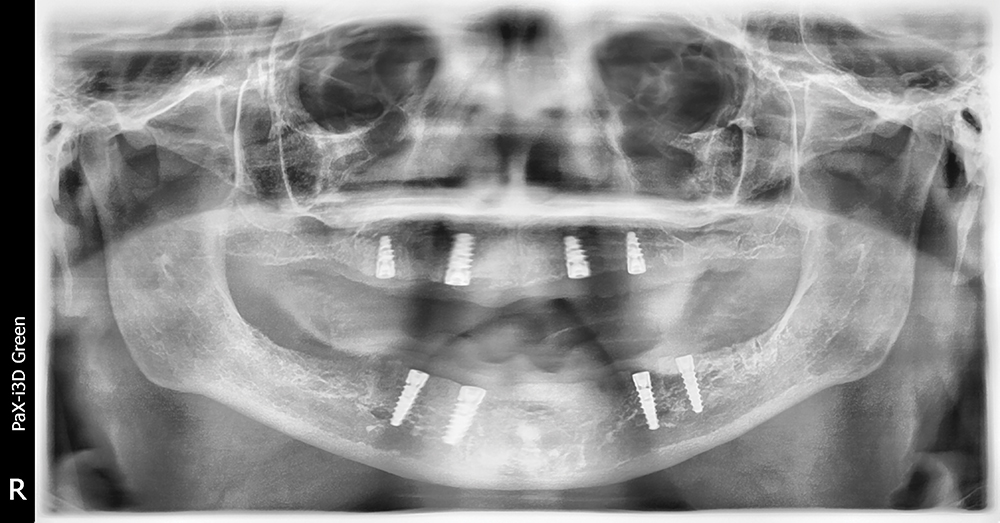

Our patient is a middle-aged female who presented with a chief complaint of ill-fitting, unstable maxillary and mandibular conventional dentures. We discussed several options, including relining her existing dentures, fabrication of new conventional dentures, implant-retained overdentures and fixed implant-supported prostheses. The patient opted for implant placement and restoration with a Locator Overdenture — which would provide an effective, economical means of addressing the patient’s needs and improving prosthetic stability and dental function.